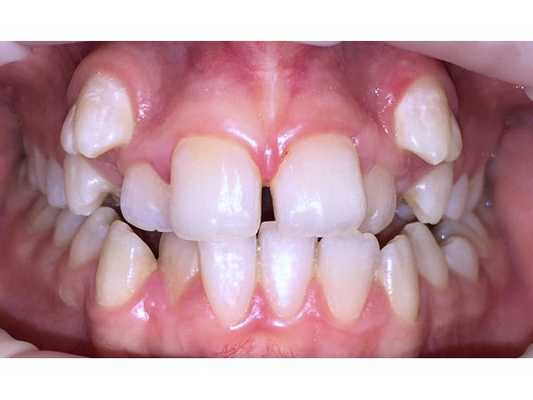

Пациентка жаловалась на эстетический дефект (выступающие клыки), затруднённое пережёвывание пищи, травму слизистой из-за накусывания щеки и губ и боли в области височно-нижнечелюстного сустава при широком открывании рта.

- Вестибулярный наклон клыков верхней челюсти (зубы расположены вне зубного ряда).

- Эндопозиция трёх резцов, т. е. их смещение или наклон кнутри от зубного ряда.

- Тесное положение зубов. . .